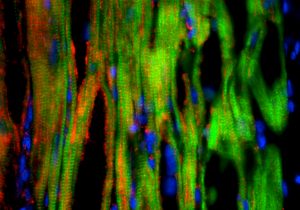

Heart muscle cells

Work from a CIRM-funded team at Stanford has moved other doctors a bit closer to this goal for heart disease. But this research will not lead to treating it, rather it could allow doctors to prevent therapies used for other diseases from causing heart disease. Joseph Wu and his team have made two discoveries that help validate the use of the iPS reprogramming technique to make patient-specific stem cells and then mature them into heart muscle cells and see how those cells react to specific drugs.

“Thirty percent of drugs in clinical trials are eventually withdrawn due to safety concerns, which often involve adverse cardiac effects,” said Wu in a press release picked up by ScienceNewsLine. “This study shows that these cells serve as a functional readout to predict how a patient’s heart might respond to particular drug treatments and identify those who should avoid certain treatments.”